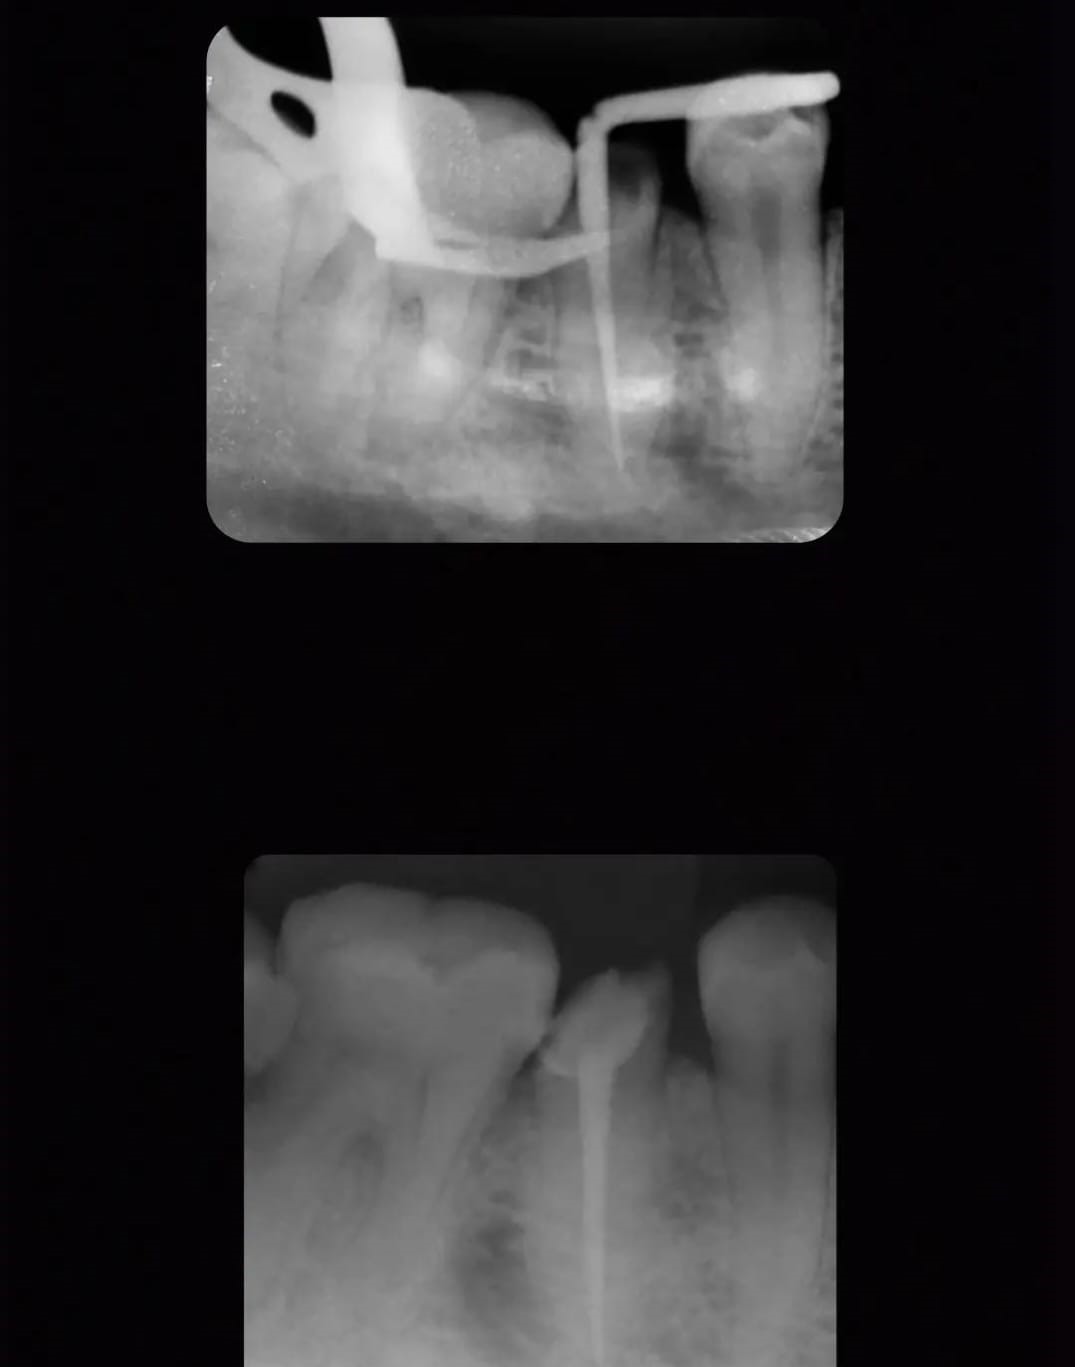

Especialidade principal. Remoção da polpa inflamada para alívio imediato da dor e preservação do dente.